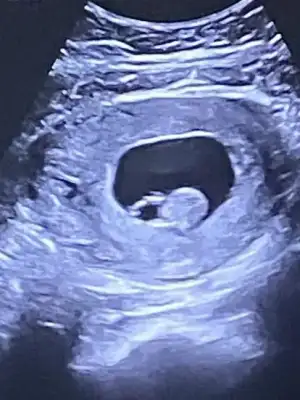

Biri sekiz diğeri ayrıntılı ultrasonda 11 haftalık canımAt bakayım ama 6-7-8 haftalık varsa onu at canım![]()

Baksana şunun kesesine canım ben erkek diyorum oval olunca Allah'ım sen sağlıkla nasip etnormal normal hıc korkma, 6mm sonrası sıkıntıymıs ..

benım ılık gun 4,3 mm di.. ilk ölçümde 5,5 mm bıraz buyuk gıbı demıstı doktor tekrar baktık 4,3mm cıktı..

Sen hemen progestani kullan ve tuvalet harici sakin kalkma yerinden dinlen.Insallah tutunacak bebis.biraz duzelince de gidip o doktoru mahvet .Bu kadar kolay mi ya basindan atip salak salak tavsiyeler vermek bir cana kastetmek!Kalp atışını dinlemedik canım gosterdi sadece haftasından biraz geride bebek geç döllenme olmuş olabilir dedi ilerleyen haftalarda karar verilir dedi. Yolk kesesi normal dedi. Bebek 7 mm. Eğer öyle bebeğimr zorla zarar verdirttilersr Allah belalarını versin bişey demiyorum